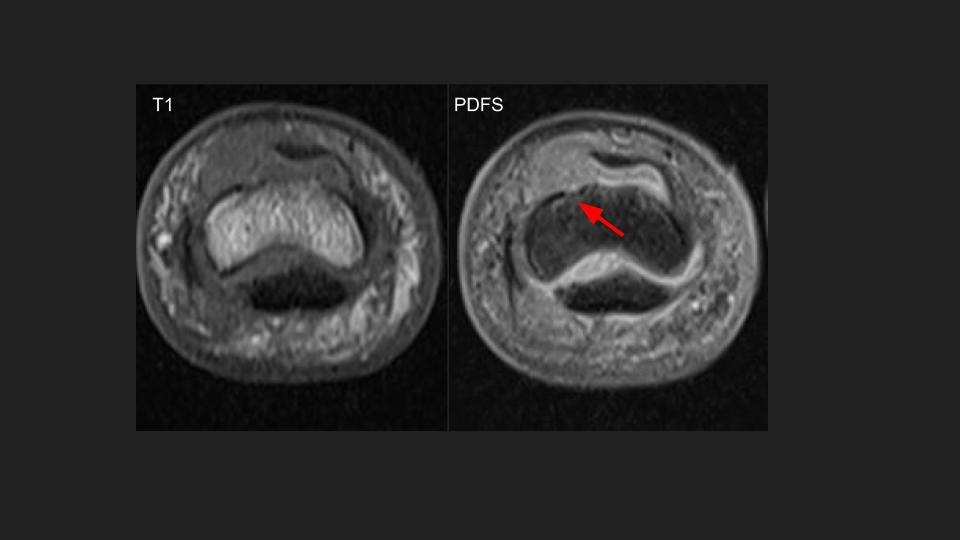

Aspirated and proven Gout of the first toe interphalangeal joint.

There is an intermediate T1 / Bright PDFS, STIR signal mass dorsal to the hallux IP with subtle erosion (arrow in short axis MRI) and no BME. No joint space narrowing, mild IPJ synovitis (not shown). XRs and US send as screenshots from referrer. She aspirated whitish greenish material from the dorsal IPJ mass/collection.